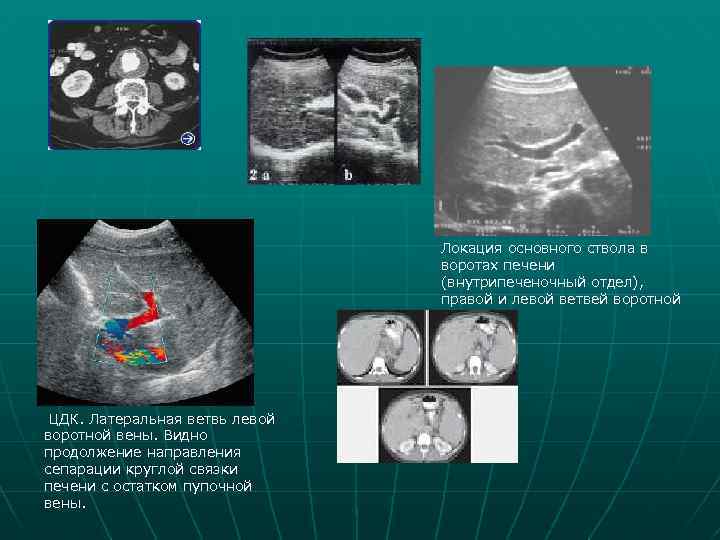

Локация основного ствола в воротах печени (внутрипеченочный отдел), правой и левой ветвей воротной вены ЦДК. Латеральная ветвь левой воротной вены. Видно продолжение направления сепарации круглой связки печени с остатком пупочной вены.